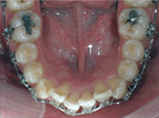

齒列擁擠的不正咬合經由擴大效果排列整齊:

Before

Proceeding

After